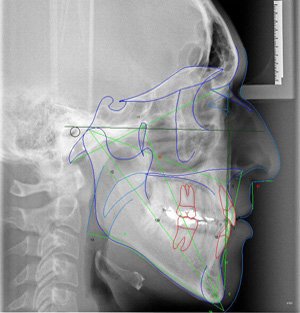

Radiografias do crânio, realizadas a uma distância pré-estabelecida, com o objetivo de diminuir distorções, com o auxílio de um artefato posicionador – cefalostato. Permite mostrar os ossos da face e crânio para avaliação do crescimento, desenvolvimento, relação esqueletal, simetria, estudo de adenóides, processos patológicos e traumáticos. São exames utilizados na prática cirúrgica e ortodôntica, como base para análises cefalométricas, tanto manual como computadorizada.